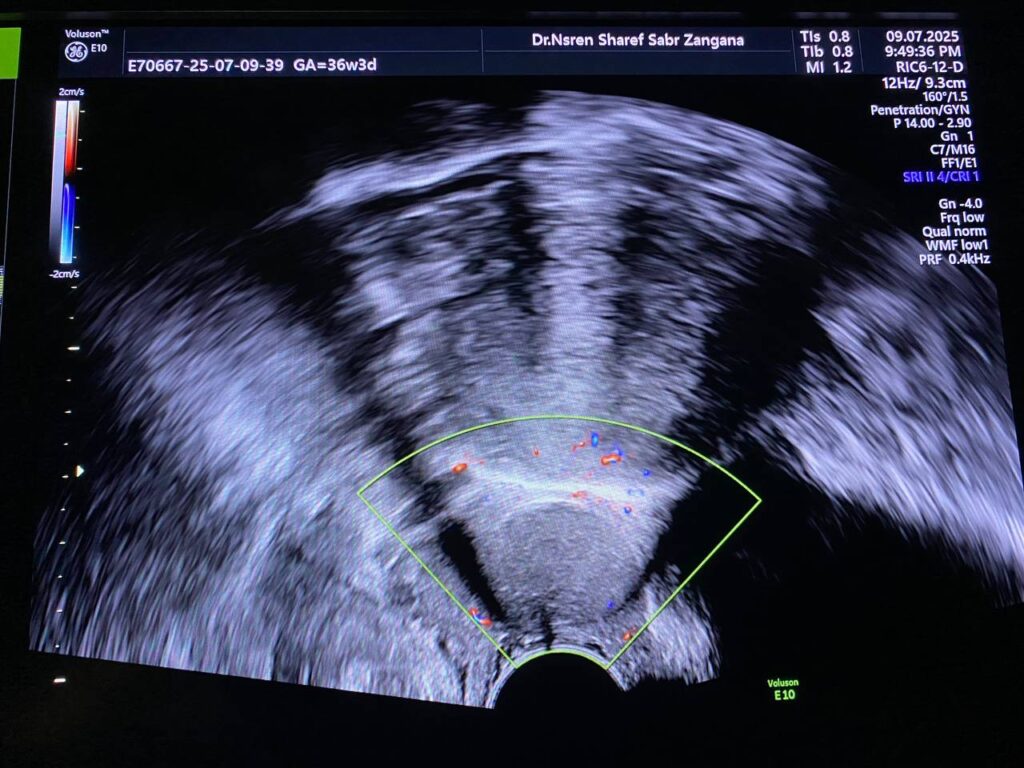

presence of well defined avascular heterogenous cystic mass 26x21mm , between the corpocervical junction and posterior urinary bladder , mostly endometriosis

presence of well defined avascular heterogenous cystic mass 26x21mm , between the corpocervical junction and posterior urinary bladder , mostly endometriosis